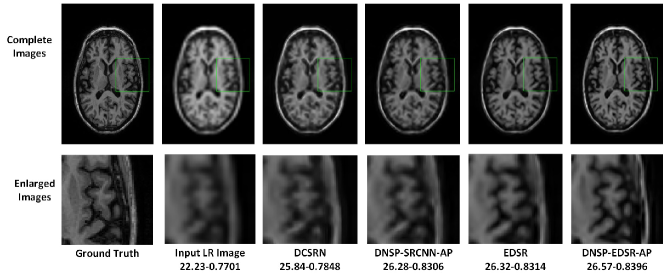

Figure 14: Comparisons of top 4 methods for an image in BW data set for scale factor of 4. A small portion of the images (marked by green rectangle) in the first row is zoomed in and shown in second row. The numerical figures constitute the respective PSNR-SSIM values.

Table II shows PSNR and SSIM values for all competing methods. Note that we used two different base networks for DNSP: 1) DNSP-SRCNN-AP - the base network is SRCNN and 2) DNSP-EDSR-AP - the base network is EDSR. Three trends emerge from the results: 1) DNSP-EDSR-AP outperforms the competition, 2) DNSP-SRCNN-AP does better than all the methods except EDSR, and 3) overall, deep SR methods, i.e. SRCNN, EDSR, DCSRN and DNSP perform better than other alternatives. To confirm this statistically, we performed a 2-way Analysis of Variance (ANOVA) on PSNR values for all the methods across the two datasets which is illustrated in Fig. 10. It may be inferred from Fig. 10 that deep learning methods are statistically well separated from the traditional methods and further DNSP-EDSR-AP is well separated from all the competing methods indicating the effectiveness of using prior information. Figures 11 and 12 illustrate the results of the top 4 methods w.r.t. PSNR on a sample image from BW and ADNI databases respectively for a down-sampling factor of 2 while Figures 13 and 14 show results for a down-sampling factor of 4. DNSP-EDSR-AP particularly excels in recovering fine image detail (enlarged with zoom-in boxes), thanks to data-adaptive sharpness.